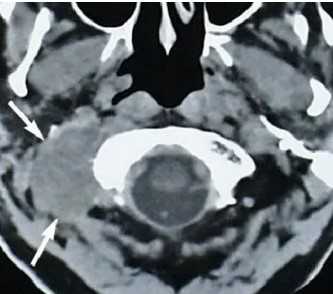

МРТ: рак простаты Т2а и Т3а (стрелки указывают на вовлеченность капсулы в опухолевый процесс)

А - магнитно-резонансная томограмма демонстрирует неровность контура капсулы левой доли простаты с распространением мягкотканного компонента за ее пределы (стрелка), Т2 ВИ. В - изображение после динамического введения гадолиния. С - после обработки компьютерной программой - явное усиление интенсивности МР-сигнала в зоне патологии, типичное для неопластического перерождения